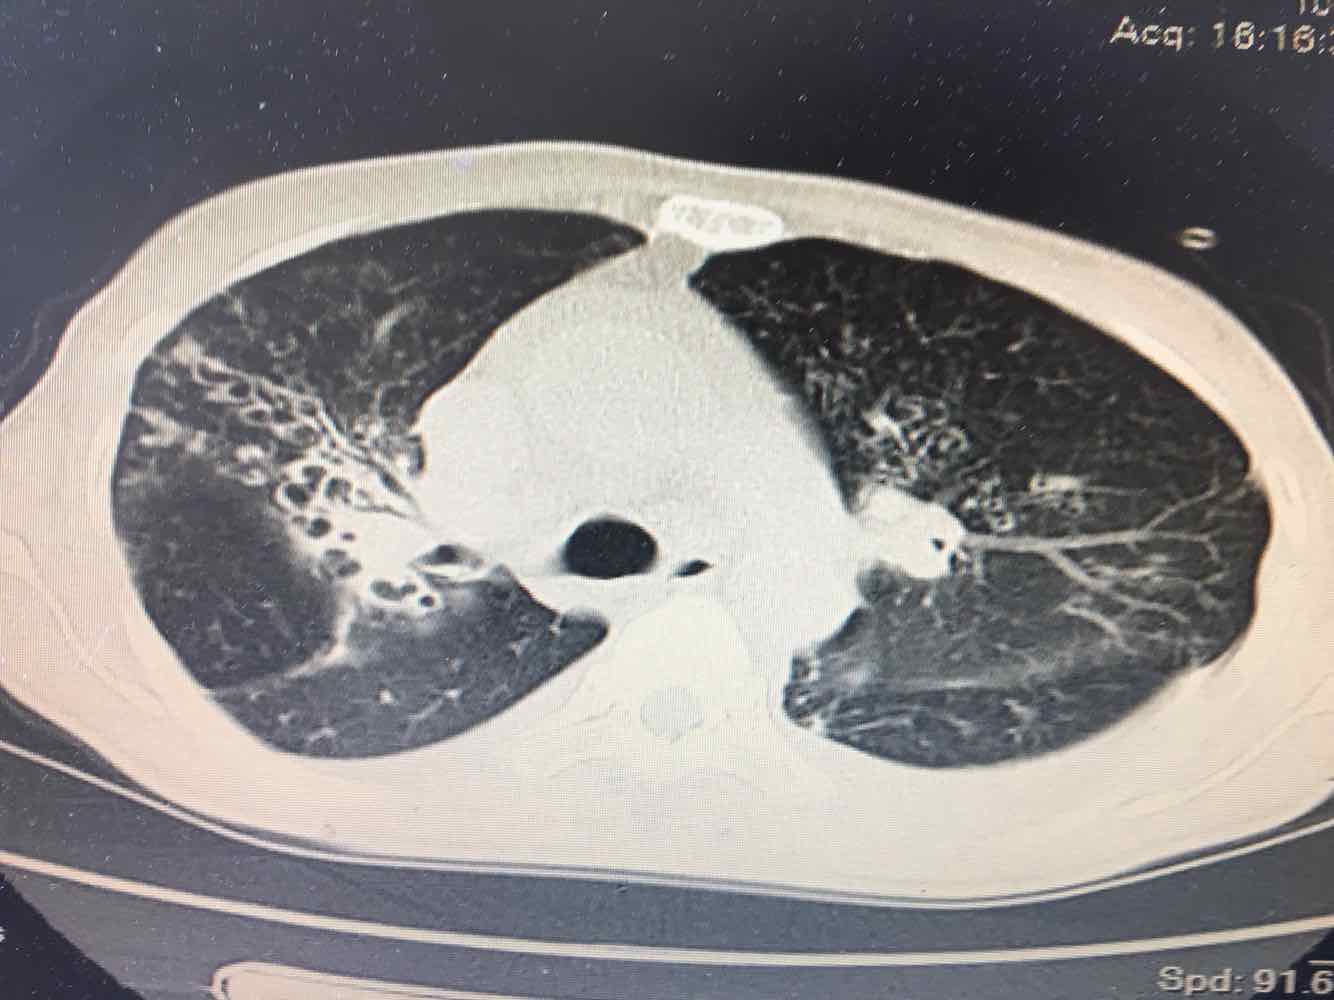

女,51岁,支气管扩张病史多年。慢性咳嗽咳痰喘息30年,加重1个月,无发热,气短为主,痰液不多,上腹不适,少尿。双肺干湿罗音。